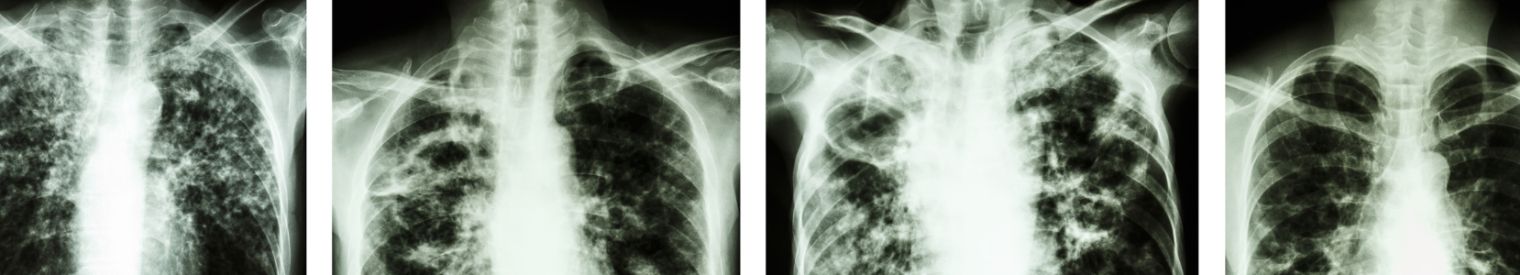

• Röntgenfoto.

Bij een röntgenfoto maken we een foto van je longen. Zo kunnen we zien of je longtuberculose hebt of niet.